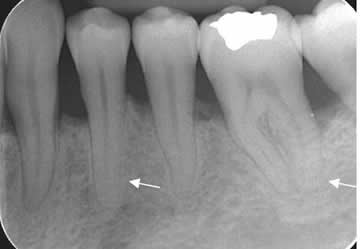

Fig 40. Enfermedad periodontal.

Rx periapical. Pérdida en la nitidez de los contornos del ligamento periodontal, por inflamación incipiente.